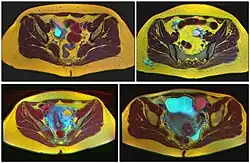

Ovarian cysts are usually diagnosed by pelvic ultrasound, CT scan, or MRI, and correlated with clinical presentation and endocrinologic tests as appropriate.[15] Ultrasound is the most important imaging modality, as abnormalities seen in a CT scan sometimes prove to be normal in ultrasound.[5][8] If a different modality is needed, then MRIs are more reliable than CT scans.[5]

Accurately differentiating an cyst from a cancer is critical to management. Medical imaging showing a simple, smooth bubble of watery liquid is characteristic of a benign cyst.[8] If the cyst is large, is multilocular, or has complex internal features, such as papillary (bumpy) projections into the cyst or solid areas inside the cyst, it is more likely to be cancerous.[13]